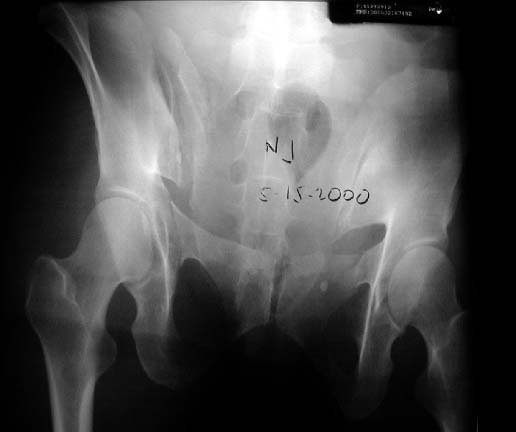

A woman in her 30's in a high speed MVC with this closed pelvic fracture. She's hemodynamically stable, no other injuries - belly, chest, and head are all fine. She also has a comminuted supracondylar femur fracture on the R side.

Preop AP

Preop Inlet

Preop Outlet

You classify it as a vertical shear. I agree that it's vertically unstable. But, the iliac wing fracture leads me to call it an LC 2 fracture. (We use the Young Burgess system down here. Someone else might call it a "crescent" fracture). I guess, like most classification systems, the YB probably has only a 60% interobserver agreement...

the enclosed ct image demonstrates her second, not upper sacral segment.

her plain pelvic radiographs indicate upper sacral dysmorphism, which has a significant impact on safe iliosacral screw insertion, regardless of imaging modality chosen to assist insertion.